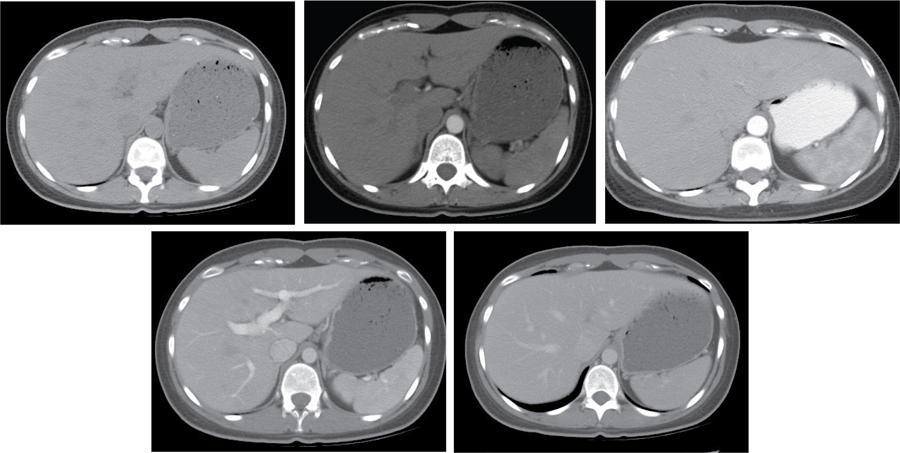

Ritu K. Kashikar, Shrinivas B. Desai, Pooja Punjani Vyas, Nilesh Doctor, Vivek Shetty Owing to advances in technology, focal liver lesions (FLLs) are increasingly encountered. Imaging particularly computed tomography (CT) and magnetic resonance imaging (MRI) play a vital role in diagnosis and characterization of FLL, thus avoiding unnecessary biopsies and interventions. Multiphase CT accurately diagnosis most liver lesions. Better soft tissue contrast and lack of ionizing radiation makes MRI a preferred modality in diagnosing FLLs. MRI with or without contrast for characterization of liver lesions regardless of preexisting liver disease has been assigned the highest rating as per American College of Radiology Appropriateness Criteria (Table 9.11.1). Solid lesions of epithelial origin Solid lesions of nonepithelial origin Pitfalls Cystic liver lesion Developmental cyst Infective cyst Miscellaneous Tmours of hepatocellular origin Tumours of nonepithelial origin Malignant cystic lesion Hepatic metastasis Ultrasound is often the initial modality for diagnosis and also the incidental detection of FLLs. Limitations to USG include the detection of small lesions less than 2 cm in size, particularly in patients who are cirrhotic or undergoing chemotherapy. Characterization of FLLs, involvement of crucial structures such as blood vessels, local staging and decisions such as operability are also not accurate with ultrasound alone and require confirmation with CT/MRI. The liver typically images in supine and left lateral positions. A curvilinear transducer with a frequency of 1.5 Hz is used. The subcostal diagonal, subcostal longitudinal or sagittal and transverse right intercostal lateral views are used. Right lobe of liver is imaged through an intercostal approach when the patient is taking deep inspiration. Subcostal view is used to image the three hepatic veins in one view. Transverse, longitudinal and oblique views of the liver are taken to image all the segments of liver. Colour and power Doppler have increased sensitivity for FLL detection, but sensitivity is still inferior to contrast-enhanced CT and MRI. The introduction of microbubble contrast agents (CAs) and the development of contrast-specific techniques have opened new perspectives in ultrasound of the liver. The technique is based on a new class of intravascular microbubble agents which contain perfluoro gases instead of air. This when combined with scanning modes sensitive to harmonic responses of microbubbles enable tissue signal suppression. The advent of the multislice technique and isotropic voxel have improved the spatial resolution of CT, allowing the recognition of small FLLs in difficult areas. Multislice CT has a sensitivity and specificity in the diagnosis of malignant FLLs of 63% and 64%, and 92 and 97%, respectively. Contrast media administration with dose based on the patient’s weight (approximately 600 mg iodine/kg of bodyweight), an iodine content of 350–400 mg/mL and a high injection rate of 4–5 mL/s are imperative to attain good contrast enhancement. Region of interest in the abdominal aorta and a threshold of 100 HU allows correct timing for threshold. A delay of approximately 18 s after the threshold provides the first arterial phase, allowing detection of hypervascular FLLs such as hepatocellular carcinoma (HCC). The late arterial phase is obtained approximately 10 s after the early arterial phase and shows progressive enhancement of hypervascular lesions, improving detection rate, while the optimal hepatic enhancement in the portal phase is reached approximately 50–60 s after the threshold. Portal venous thrombi are also best detected in this phase. The venous phase aids in the detection of washout, hepatic venous thrombosis. Delayed phase is often required in lesions such as cholangiocarcinoma and haemangioma, which show progressive enhancement (Table 9.11.2, Fig. 9.11.1). Delayed phase images are required for tumours such as cholangiocarcinoma and large haemangiomas, which reveal delayed enhancement. As mentioned previously, MRI is the modality of choice in diagnosis of FLLs. Most FLLs appear hyperintense on T2W1 images with varying intensity depending upon the water content and flow dynamics. FLLs are typically hypointense on T1W1 images with the exception of fat containing, haemorrhagic lesions and those containing chelates of metals like regenerating/dysplastic nodules. In- and opposed-phase images help in detection of intralesional fat. Diffusion-weighted images are beneficial particularly in noncirrhotic population and best suited in detection of metastasis. Postcontrast images obtained with extracellular agents are parallel to those obtained with CT (Fig. 9.11.2). The pre- and postcontrast MRI protocol is mentioned in Table 9.11.3. T2-weighted single-shot fast spin-echo (SE) T1-weighted in- and opposed-phase GRE Dynamic 3D T1-weighted FS spoiled GRE (in hepatic arterial, portal venous and equilibrium phases) There are two main categories of CAs used in liver imaging – the extracellular and the hepatocyte-specific (Fig. 9.11.3). Extracellular agents are more widely used and provide information similar to contrast-enhanced CT study. The advantage of the other category of CAs, that is, hepatocyte-specific agents, is the ability to provide this extracellular information with added benefit of delayed phase information. Tumours of hepatocellular origin with functioning hepatocytes take up and biliary excretion with take up and retain these agents appearing isointense to background liver. Lesions without functioning hepatocytes fail to retain contrast and hence appear hypointense to background liver on delayed phase. This allows better detection and characterization of focal liver lesion particularly those lesser than 2 cm (Table 9.11.4). Haemangioma is the most common benign hepatic tumour. The incidence in general population varies from 1% to 20%. Females have a higher preponderance with variable female to male ratios of 2:1 to 5:1. Imaging in particular MRI has high reliability in diagnosing classic haemangioma. The sensitivity and specificity of MRI is greater than 90% in diagnosis. The aetiology of haemangioma is unknown. Since haemangiomas are known to run in families, a genetic origin has been implicated, while other mesenchymal tumours are thought to be congenital. Most patients are asymptomatic and often the lesion is discovered as an incidental finding. Pain in the right upper abdomen is the most common complaint; others include loss of appetite, nausea, vomiting and abdominal discomfort. Symptoms are usually seen in large haemangiomas or those with complications. Liver function tests and tumour markers like AFP and CA19.9 are within normal limits. Blood-filled cavities of varying sizes lined by flat endothelial cells and supported by fibrous connective tissue are seen on histology. Three histological subtypes have been described: the capillary haemangioma, the cavernous haemangioma and the sclerosing haemangioma. The imaging features of a haemangioma depend on its size; typical haemangiomas are mostly less than 3 cm in diameter. Haemangiomas are hyperechogenic, homogeneous lesion presenting a posterior acoustic enhancement (Fig. 9.11.3). The hyperechogenicity of haemangiomas is related to the interfaces between vascular spaces, fibrous stroma and the slow blood flow. Typically, haemangiomas have slow flow and hence do not show vascularity on colour or power Doppler. The sensitivity and specificity of ultrasound in differentiating haemangioma from other malignant lesions are high, with values of approximately 94.1% and 80%, respectively, for lesions less than 3 cm in diameter. Unlike HCC, no flow is seen on colour Doppler. A peripheral echogenic rim around hypoechoic lesions can suggest haemangioma. On the contrary, perilesional hypoechoic rim called the target sign is seen in lesions such as metastasis (Table 9.11.5). Adenomas can be distinguished on the basis of the absence of posterior acoustic enhancement and characteristic pattern of peripheral vascularity seen in adenoma. Another differential diagnosis to be considered is focal nodular hyperplasia (FNH), which has the characteristic ‘spoke-wheel sign’. Contrast-enhanced ultrasound (CEUS) improves specificity for the diagnosis of haemangioma. The vascularity pattern with contrast-enhanced USG is similar to that seen with CT. The typical hemangioma (HH) shows peripheral nodular enhancement in the arterial phase with complete (but sometimes incomplete) centripetal filling in the portal venous and late phases. This particular pattern of enhancement helps in differentiating haemangiomas from other lesions like adenomas, FNH, HCC or metastasis. This characteristic enhancement pattern has a sensitivity of 98% for histologically proven HH. One should be aware that an HH can rarely have a centrifugal enhancement. Computed tomographic (CT) findings consist of a hypoattenuating lesion on nonenhanced images. Haemangiomas show peripheral discontinuous nodular enhancement on arterial phase of dynamic contrast-enhanced CT. The density of the nodules is equivalent to that of the aorta. Centripetal filling with is seen on venous phase, which progresses to uniform enhancement. The enhancement persists on delayed phase (Fig. 9.11.4). Washout of contrast on delayed phase is not seen in haemangioma and if seen, alternate diagnosis must be considered. This classical pattern of enhancement cannot be highlighted in very small lesions of less than 5 mm, which can be difficult to characterize. In patients with severe fatty infiltration of the liver, HH can appear hyperdense relative to the adjacent liver parenchyma on nonenhanced scan. Haemangiomas are hyperintense on T2-weighted images, which is identical to that of cerebrospinal fluid. T2 hyperintense signal is classically described as ‘light bulb bright’. Malignant lesions of the liver do not appear as bright on T2W1 images. They appear hypointense to adjacent liver on T1-weighted images. Long relaxation T2W1 images further improve accuracy in diagnosis of haemangiomas and help in differentiation from metastasis. Haemangiomas, unlike other liver lesions retain hyperintense signal on long relaxation T2W1 images. A threshold of 112 ms has 92% accuracy, 96% sensitivity and 87% specificity for differentiating haemangiomas from metastasis. On gadolinium administration, the enhancement pattern is similar to that seen with iodinated contrast on CT. Classic enhancement pattern in combination with characteristic T2 appearance are diagnostic for haemangioma (Fig. 9.11.5). Certain pitfalls exist in diagnosing haemangiomas using gadoxetate disodium. Due to the lack of hepatocytes, haemangiomas appear hypointense to the background liver on delayed hepatocyte phase and mimicking malignant process (Table 9.11.6). Lesions shown peripheral nodular arterial enhancement (Table 9.11.7): On fluorodeoxyglucose-positron emission tomography (FDG-PET)/CT, most hepatic haemangiomas appear low-attenuation lesions with FDG avidity equal to background liver parenchyma and are easily determined to be benign. However, a small percentage of haemangiomas may be FDG-avid. If an FDG-avid hepatic lesion demonstrates the characteristic enhancement pattern, this is consistent with an FDG-avid haemangioma. Technetium-99m pertechnetate-labelled red blood cell scintigraphy has high specificity in the diagnosis of haemangiomas. In this technique, there is decreased activity in haemangiomas on early images and increased activity on delayed blood pool images. Therefore, radionuclide scintigraphy has a sensitivity of 78% and an accuracy of 80% and may be a valuable tool when the diagnosis cannot be achieved with other imaging modalities. Large haemangiomas are often heterogeneous with internal clefts and septae. They are termed as giant haemangiomas when they exceed 4 cm in diameter. Discrepancies are there in definition with some authors defining giant haemangiomas as lesions greater than 6 cm or 12 cm in diameter. These may cause symptoms of abdominal pain and distension. These haemangiomas demonstrate changes such as haemorrhage, thrombosis, extensive hyalinization, liquefaction and fibrosis. The central cleft-like area may be due to cystic degeneration or liquefaction. On USG, they reveal heterogeneous echotexture. They are hypoattenuating and heterogeneous on nonenhanced CT with central areas of low attenuation. After intravenous administration of contrast material, the typical early, peripheral and globular enhancement is observed. These may show irregular or ‘flame-shaped’ discontinuous peripheral enhancement as opposed to typical nodular enhancement pattern seen in smaller haemangiomas. Although centripetal pattern of enhancement is seen during the venous and delayed phases, the filling-in incomplete. Central scars are defined in this subset of haemangiomas (Fig. 9.11.6). At MRI, T2-weighted images show a markedly hyperintense cleft-like area and some hypointense internal septa within a hyperintense mass. On delayed phase, incomplete filling and central scar are seen similar to CT (Fig. 9.11.7). Complications include intratumoural haemorrhage, inflammatory changes or consumptive coagulopathy (Kasabach–Merritt syndrome). These may warrant management such as arterial embolization or resection. This pattern is seen 16% of all haemangiomas, and is seen more often in small haemangiomas (42% of haemangiomas) <1 cm in diameter. CT and MRI show immediate homogeneous enhancement at arterial phase CT or contrast-enhanced MRI. The size of the blood spaces is the reason for difference in enhancement pattern. Smaller the lesion, smaller the size of blood spaces and faster the rate of spread of contrast material. These lesions usually show perilesional halo of hyperenhancement on the late arterial phase, which is believed to be due to arteriovenous shunting. Rapid arterial enhancement makes these haemangiomas difficult to distinguish from hypervascular metastasis (Table 9.11.8). However, washout of contrast is seen from haemangiomas on delayed phase (Fig. 9.11.8). Hepatic haemangiomas rarely demonstrate calcifications, while haemangiomas in other locations frequently demonstrate phleboliths. Calcified haemangiomas are mostly found incidentally. Calcifications may occur in the marginal or central portion of the lesion and consists of multiple spotty calcifications, which correspond to phleboliths. However, large, organized calcifications are also possible. Some calcified haemangiomas may demonstrate poor enhancement. Hyalinized hepatic haemangiomas are rare. It has been suggested that hyalinization represents an end stage of haemangioma evolution. These haemangiomas are usually asymptomatic. The radiological features of a haemangioma are completely altered ones hyalinization occurs; hence biopsy is often mandatory for diagnosis. Hyalinized haemangiomas show only slight high signal intensity on T2W1 images. There is lack of early enhancement on dynamic contrast-enhanced images (Fig. 9.11.9). Fluid–fluid levels within haemangiomas are very rare. Fluid–fluid levels are seen both with CT and MRI with inferior layer representing the red blood cells and superior layer unclotted serous blood. Dependent hyperdensity/T1 hyperintensities can be seen corresponding with dependent haemorrhage. Pedunculated haemangiomas are very rare. They can be asymptomatic or complicated by subacute torsion and infarction. Typical enhancement pattern and signal on T1 and T2W1 images are clues to the diagnosis. Capsular retraction is usually associated with malignant tumours such as cholangiocarcinoma, epithelioid haemangioendothelioma or metastases. Rarely, it has been seen in haemangiomas. A possible mechanism could be fibrous degeneration. Multiple haemangiomas are seen in 10% of cases and usually show classical imaging features. Fatty infiltration of liver may alter the imaging appearances of lesions. Haemangiomas appear slightly hyperechoic, isoechoic or hypoechoic relative to the fatty liver. At nonenhanced CT, the lesion may be hyperattenuating relative to the liver. Contrast-enhanced CT shows peripheral enhancement and delayed filling, an appearance similar to that of a haemangioma in a normal liver. Haemangiomas are less common in setting of cirrhosis and may be difficult to diagnose due to sclerosis. Complications are seen in 4.5%–19.7% and often seen in large lesions such as inflammation, coagulation within can lead to systemic disorders, haemorrhage would lead to haemoperitoneum, volvulus and adjacent organ compression. Irrespective of the size, treatment is indicated only for haemangiomas with significant symptoms, those developing complications, or when there is an inability to exclude malignancy. Attempt should be made to exclude other causes of the patient’s symptoms. The term focal nodular hyperplasia (FNH) was introduced in 1958 by Edmondson. In 1995, the International Working Party classified FNH with other regenerative lesions, and not a neoplastic lesion. It is defined as a nodule consisting of normal appearing hepatocytes occurring in a histologically normal liver. It is the second most common tumour of the liver after haemangioma with a reported prevalence of 0.9%. The lesion is more commonly seen in females with female to male ratio of 8:1. Multiplicity is seen in 20% of patients. The combination of multiple FNH lesions and haemangiomas is considered to be multiple FNH syndrome. Vascular malformation and vascular injury have been suggested as the underlying mechanism. An association with steroids has been denied more recently. FNH has been classified as classic and nonclassic varieties. These have been discussed in Table 9.11.9. Classic FNH is characterized by abnormal nodular architecture, malformed vessels and cholangiolar proliferation. Nonclassic FNH lesions lack one of the following classic features – nodular abnormal architecture or malformed vessels – but always show bile ductular proliferation. Classic FNH on gross appearance shows lobulated contours with multiple nodules surrounded by fibrous septae originating from a central scar, which contains a vascular malformation. On histopathology, nodular hyperplastic parenchyma is seen in classic FNH. Circular or short fibrous septae surround these nodules completely or incompletely. Thickening of the hepatic plates is seen. Fibrous connective tissue, cholangiolar proliferation with surrounding inflammatory infiltrates and malformed arteries, capillaries, vascular channels of undetermined type and veins are seen in the central scar. The arterial blood in FNH shows centrifugal distribution from anomalous central arteries. Fatty infiltration is seen in approximately 50% of lesions, while signs of hepatic steatosis are seen in approximately 20% of cases with classic FNH. Variable amounts of Kupffer cells are seen in both classic and nonclassic variants. Nonclassic FNH is heterogeneous and on gross appearance resembles adenomas in most cases, with vaguely lobulated contours and lack of a macroscopic central scar. The histology varies with subtypes. Subtypes of nonclassic FNH include telangiectatic type, mixed hyperplastic and adenomatous forms and FNH with cytologic atypia. The histological features of these are described in Table 9.11.10. At US, typical FNH is often not well visualized. The lesions may be slightly hypoechoic, isoechoic or slightly hyperechoic. The compressed liver tissue form a hypoechoic halo around the lesion, which appears more prominent in patients with fatty infiltration. A prominent central scar may improve the conspicuity of the lesions. Use of colour and power Doppler US shows vascularity in suspected FNH. On contrast-enhanced USG, FNH is hyperenhancing in the arterial and portal venous phases in more than 90% of cases. The arterial enhancement patterns include central (60%–70% of cases) or eccentric (<20% of cases) with centrifugal filling, but sometimes are homogeneous. Multiphase CT is an excellent modality for detection and characterization of FNH. These lesions classically show a lobulated contour. At unenhanced CT, the lesions are either hypoattenuating or isoattenuating to the surrounding liver. In the arterial phase, the lesions show homogeneous intense enhancement except the central scar and fibrous septa. In the portal and later phases, the lesions become more isoattenuating with the surrounding liver. The central scar reveals enhancement on delayed phase (Fig. 9.11.10). This feature helps distinguish from other lesions with central scar-like fibrolamellar carcinoma. A vascular malformation can be seen in the central scar in some cases (Fig. 9.11.11). There may be enlarged hepatic veins in the vicinity of the mass. FNH do not have portal venous drainage. The drainage is essentially into hepatic venules, hence the enlarged adjacent veins. The central scar is often not identified in small FNH lesions. In a study, 80% of FNH lesions less than 3 cm lacked visible central scar. The sensitivity and specificity of MRI in diagnosis of FNH are 70% and 98%, respectively. The central scar is more often detected with MRI than with CT (78% and 60%, respectively). FNH is typically iso- or hypointense on T1-weighted images (94%–100%) and is slightly hyperintense or isointense on T2-weighted images (94%–100%). The lesions may not be very conspicuous on T2W1 images. The central scar is hyperintense on T2-weighted images in 84% of cases. FNH shows intense homogeneous enhancement in the arterial phase. The enhancement pattern in arterial phase may be nodular, resembling a popcorn, the result of intralesional fibrous septae. Mosaic pattern of heterogeneous enhancement seen in malignant lesions is not seen in FNH. Central vascular malformation may be seen in early phases. These lesions classically fade to isointensity on delayed phase with the exception of the central scar (Fig. 9.11.12). FNH may show a pseudocapsule, which results from compression of the surrounding liver parenchyma by the FNH, perilesional vessels and inflammatory reaction. The pseudocapsule may show enhancement on delayed contrast-enhanced images. A central scar is present at imaging in most patients with FNH. The central scar is hyperintense on T2W1 and hypointense on T1W1 images. The presence of inflammation and vessels within the scar are responsible for the hyperintense signal (Fig. 9.11.13). The scar does not enhance on early phases of contrast study and shows enhancement on delayed phases of dynamic study. The scar is absent in 30% of cases. The hepatocyte-specific CA gadoxetate disodium can be useful in distinguishing FNH from other lesions like adenomas. Densely packed functioning hepatocytes and abnormal blind-ending bile ductules in FNH result in contrast retention and delayed biliary excretion. FNH often shows enhancement on delayed images using gadoxetate disodium, and along with radiating fibrous septae, it may result in a characteristic spoke-wheel appearance. On the contrary, hepatocellular adenomas (HCAs) are usually hypointense to liver on hepatocyte phase images because they lack bile ductules. Superparamagnetic iron oxide (SPIO) is a negative reticuloendothelial-specific CA taken up primarily by the hepatosplenic Kupffer cells. This agent shortens T2 relaxation time predominantly, leading to a significant decrease of SI of normal hepatic. FNH contains Kupffer cells and hence shows significant signal drop after administering SPIO. This CA is, however, not commonly used particularly with advent and increased usage of hepatocyte-specific agents (Table 9.11.11). These lesions have high signal intensity on T2-weighted images, a central scar with low signal intensity on T2-weighted images, a prominent pseudocapsule and incomplete intense enhancement of the lesion. Extreme heterogeneity can be seen in these lesions leading to difficulty in distinguishing from malignant lesions such as HCC and cholangiocarcinoma. Biopsy and histopathology diagnosis are often needed in this subset. Telangiectatic FNH may show areas of haemorrhage. A French study has reported an association of 23% between FNH and haemangiomas. The incidence of coexistence of FNH and adenoma is lower (3.6%). There have also been reports of rare associations of FNH with other types of vascular anomalies like congenital absence of the portal vein, inflammatory pseudotumours of the liver, hepatic vein thrombosis and intrahepatic arteriovenous shunting. Imaging differentials include HCA and other lesions with central scar like fibrolamellar carcinoma, HCC and giant haemangiomas (Table 9.11.12). FNH shows intense arterial phase enhancement and isodensity/isointensity on delayed phase, this feature helps in distinguishing from adenoma, which usually are hypoattenuating on the delayed phase. T1 hyperintensity seen in adenomas is not seen on FNH. Biopsy is recommended in cases where radiological features are atypical and distinguishing from malignant lesions like HCC cannot be made on the basis of imaging findings alone. As there is no risk of malignant transformation and complications are rare, FNH does not need treatment. Patients with large FNH causing compression of adjacent organs or occurrence of torsion in a pedunculated FNH may need surgical resection. Also, patients with diagnostic dilemma may be considered as surgical candidates. Adenoma is a less common benign primary neoplasm of the liver. Women of childbearing age taking oral contraceptives are considered at highest risk; however, it can occur in other women as well as men. Hepatic adenomas (HAs) were particularly associated with the use of older generation of OC pills with high-oestrogen content. Adenomas have also been reported to occur in men secondary to anabolic steroid/androgen use. Clomiphene, danazol and testosterone in patients with Fanconi anaemia (FA) and without FA, Klinefelter’s syndrome, glycogen storage disorders (GSDs) I, III and IV, alcohol and metabolic syndrome are other hormonal therapies and conditions associated with adenoma. Development of >10 adenomas in a patient is defined as hepatocellular adenomatosis (Fig. 9.11.14). Germline mutations of hepatocyte nuclear factor (HNF)-1 alpha and patients with type 3 maturity onset diabetes of young (MODY-3) may predispose. HCA has been categorized into three distinct subtypes based on genetic and pathologic features. These have been discussed in Table 9.11.13. Some exhibit both β-catenin activation and inflammatory features. Patients are usually asymptomatic at the time of diagnosis but some present with abdominal pain, haemorrhage, abnormal liver function tests or seldom with a palpable mass. HCA associated with haemorrhage may present with acute abdominal pain, elevated liver enzymes and hypovolemic shock. Signs of chronic anaemia and/or ‘systemic inflammatory syndrome’, characterized by fever, leukocytosis and elevated serum levels of C-reactive protein can be seen in patients with inflammatory HCA. Inflammatory HCAs are associated with a definitive increased risk of bleeding (>30%) and a risk of malignant transformation (5%–10%). The highest predilection for malignant transformation of all HCAs is seen in β-catenin activated subtype. On gross appearance, adenomas are well-circumscribed often encapsulated lesions with size varying between 1 and 30 cm. Lesions may be solitary or multifocal. They typically arise in nonfibrotic liver, however, the inflammatory subtype has been reported in the background of cirrhosis The cut surface of HA may be tan-yellow or red-brown depending upon the presence of steatosis or peliosis/haemorrhage/old haemorrhage, respectively. Sheets of benign-appearing hepatocytes with interspersed thin-walled, unpaired arteries are classically seen in HCA. Other variable features are steatosis, inflammatory cell infiltrate, sinusoidal dilatation, myxoid changes and presence of pigments such as bile pigment, lipofuscin or Dubin–Johnson-like pigment (Table 9.11.14). The typical small HCA is isoechoic in comparison to the surrounding liver parenchyma. Adenomas with high lipid content are hyperechoic on ultrasound. Intratumoural haemorrhage can also result in increased echogenicity and heterogeneity, or cystic areas. Calcifications are seen as hyperechoic foci with acoustic shadowing. Peripheral peritumoural vessels and intratumoural vessels with a flat continuous or triphasic form are seen on colour Doppler. FNH does not show this pattern of vascularity and hence this finding may be useful in distinguishing the two disease entities. On contrast-enhanced USG, arterial phase reveals centripetal or diffuse enhancement. Telangiectatic HCA with or without inflammation typically exhibit iso- or hyperenhancement in comparison to the surrounding liver parenchyma. Hypoenhancement is seen in portal venous phase with delayed washout in all subtypes. USG and contrast-enhanced USG features of histologic subtypes have been described. HNF-1α-inactivated HCAs are hyperechoic due to fat content and may be misdiagnosed as haemangiomas. The enhancement pattern is however that of arterial enhancement. With venous washout in contrast to haemangiomas which show portal venous hyperenhancement. On CEUS, telangiectatic HCA with or without inflammatory changes shows central multilocular vessel supply similar to FNH. These lesions might show centrifugal hyperenhancement during the early arterial phase which may persist on portal venous phase. Nevertheless, most adenomas are not specifically diagnosed at US and are usually further evaluated with CT or MRI. Multiphase CT is a good diagnostic modality in diagnosis of HCA. Fat or haemorrhage can easily be identified on unenhanced images. CT evidence of fat within the adenoma is seen in only about 10% of cases. Lesions show strong arterial enhancement and subcapsular feeding vessels. Enhancement is more heterogeneous in larger tumours and those with internal haemorrhage. The enhancement usually does not persist in adenomas because of arteriovenous shunting (Fig. 9.11.15). MRI is the modality of choice in diagnosis of adenomas and distinguishing various subtypes. Although the lesions can reveal varying signal on T1W1 images, recent reports have suggested that most adenomas are bright on T1-weighted images, 77% of cases in a study by Paulson et al. Other studies have, however, lesser incidence of T1 hyperintensity varying from 35% to 59%. Heterogeneous signal on TW1 images may be due to areas of increased signal intensity resulting from fat (36%–77% of cases in different series) and haemorrhage (52%–93%). Forty-seven to seventy-four per cent of HCAs are predominantly hyperintense relative to liver on T2-weighted images (Fig. 9.11.16). Majority of lesions are, however, heterogeneous owing to areas of haemorrhage and necrosis. Contrast-enhanced dynamic MR study shows early enhancement with peripheral subcapsular vessels. MR appearances can vary depending on the histological subtype (Table 9.11.15). On plain MRI, inflammatory HCA is often hyperintense on T2W images and hypointense on T1W sequence corresponding to areas of sinusoidal dilatation and inflammatory infiltrates. Foci of fat appear as areas of signal drop on opposed-phase images. They are hypervascular masses with persistent enhancement on dynamic study. Variable update of contrast especially at the periphery may be seen on hepatobiliary phase. Marked T2 hyperintense signal with persistent delayed enhancement has high sensitivity and specificity of 85% and 87%, respectively, for the diagnosis of inflammatory subtype. Peripheral hyperintensity on T2W1 images reflects the abnormal ductal reaction with altered biliary excretion and has been described as ‘atoll sign’ (Fig. 9.11.17).